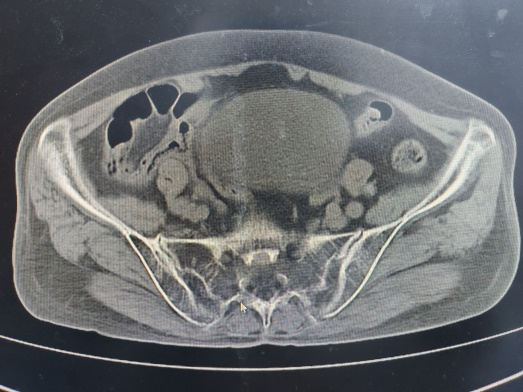

图1:切开复位内固定